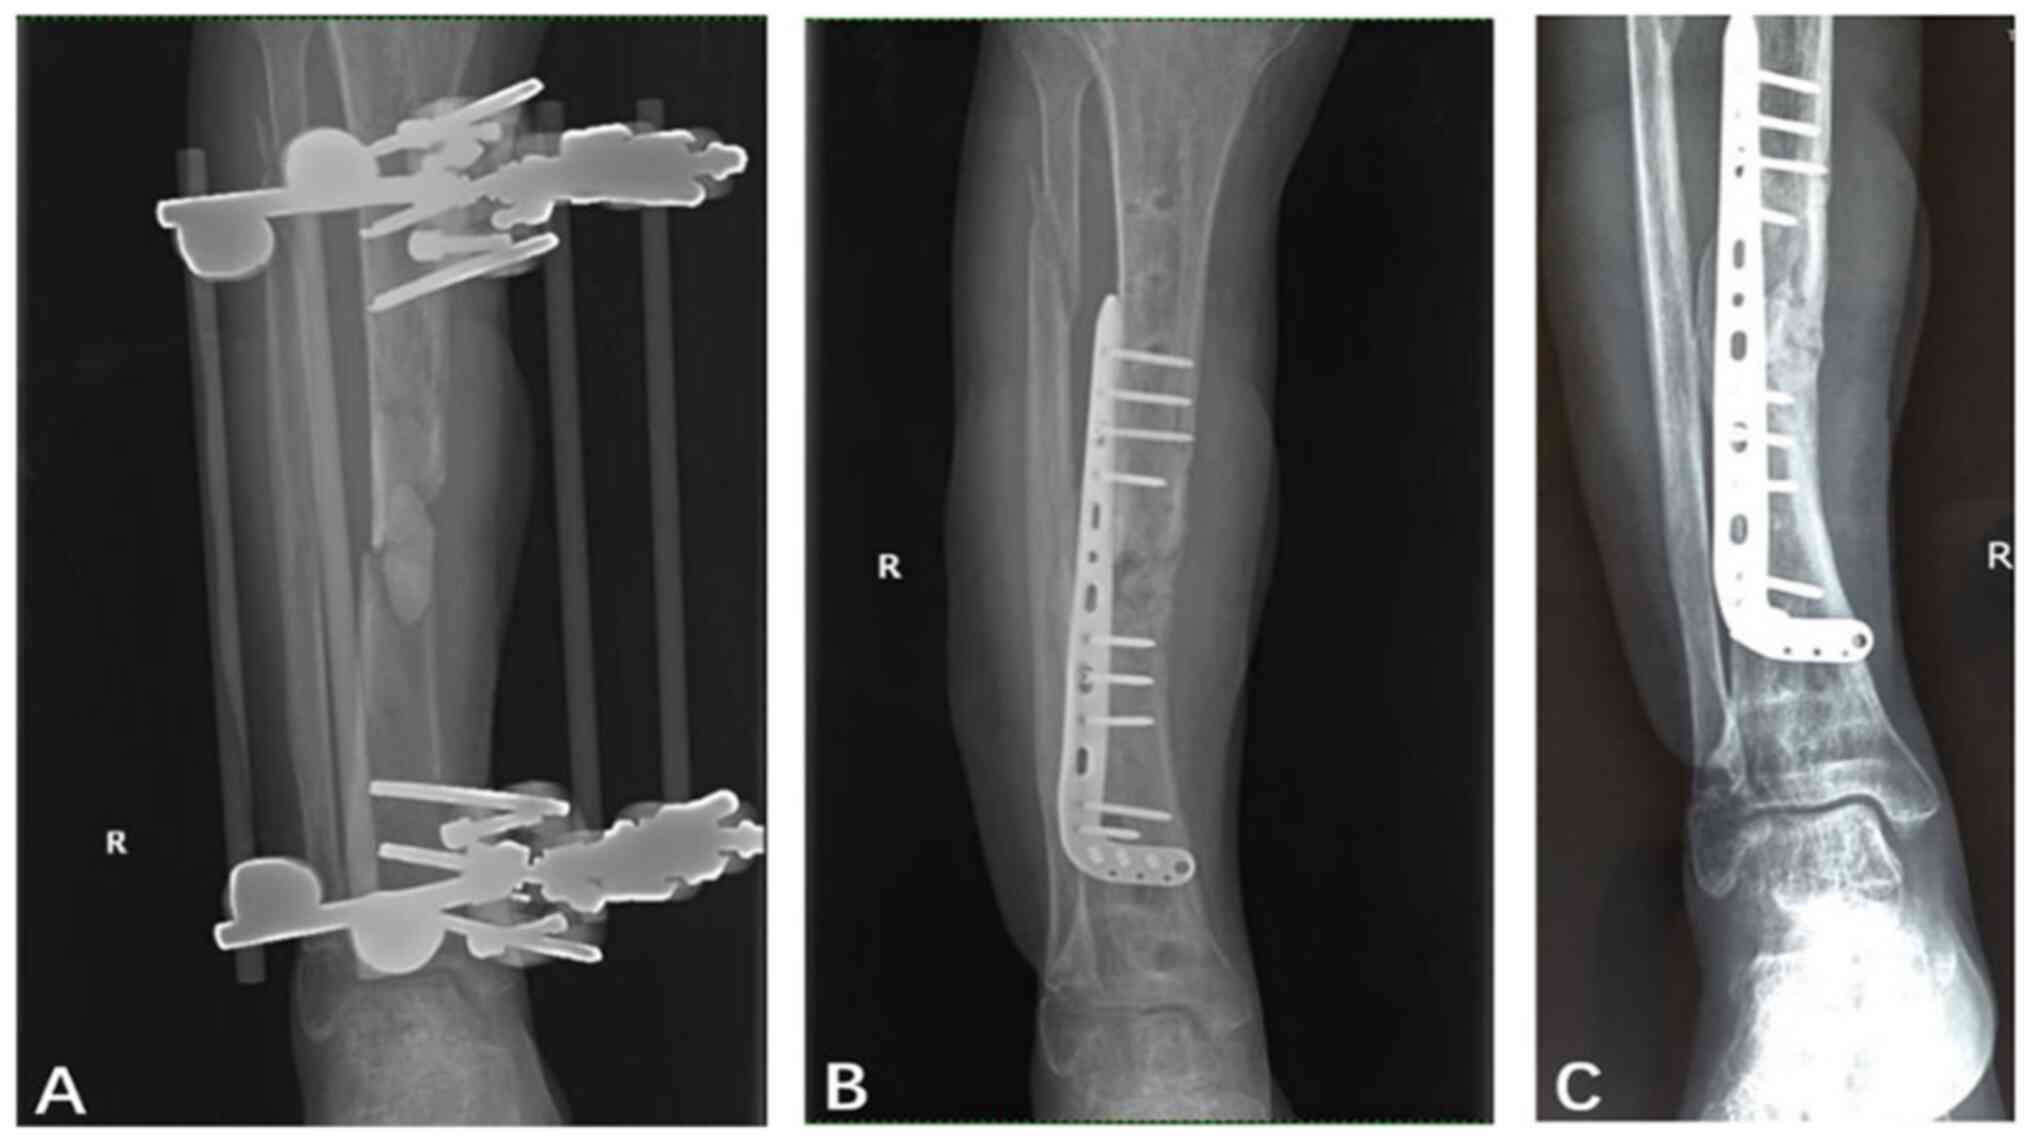

In the LP group, 3 patients (15%) had infection recurrence. In addition, 2 patients (10%) had pin-tract infection, which was a significantly lower proportion than that in the EX group (P=0.005; Table I). Furthermore, 1 patient had a loosened screw and was not subjected to any additional surgery. The patients in the LP group had a median union time of 12.3 months (Table I). However, at the 12-month follow-up, 1 patient exhibited non-union. A total of 3 patients experienced tibial shortening, which included a 5˚ mild equinus deformity in one case. In addition, a patient with a 15˚ tibial procurvatum deformity at 2 years post-surgery was treated with internal fixation. The proportion of patients in the LP group with a satisfactory functional status post-surgery was improved to 95% compared with that pre-surgery (75%). Notably, the proportion of patients with a satisfactory functional status after surgery was significantly higher in the LP group compared with the EX group (P=0.046; Table III). Representative follow-up X-ray images of patients who underwent bone grafting and changed to non-contact locking plate fixation are shown in Fig. 3.

Figure 3

Representative X-rays of a patient (no. 42) who underwent bone grafting and changed to an external non-contact locking plate. (A) Cement spacer placed in the bone defect using unilateral external fixation to provide tibial stability before the second-stage surgery. (B) Bone defect filled with autogenous iliac bone grafts and callus formation 3 months after the second-stage surgery in which the external fixator was changed to an external non-contact locking plate. (C) Recovered continuity of the cortical bone 1 year after the second-stage surgery. R, right.